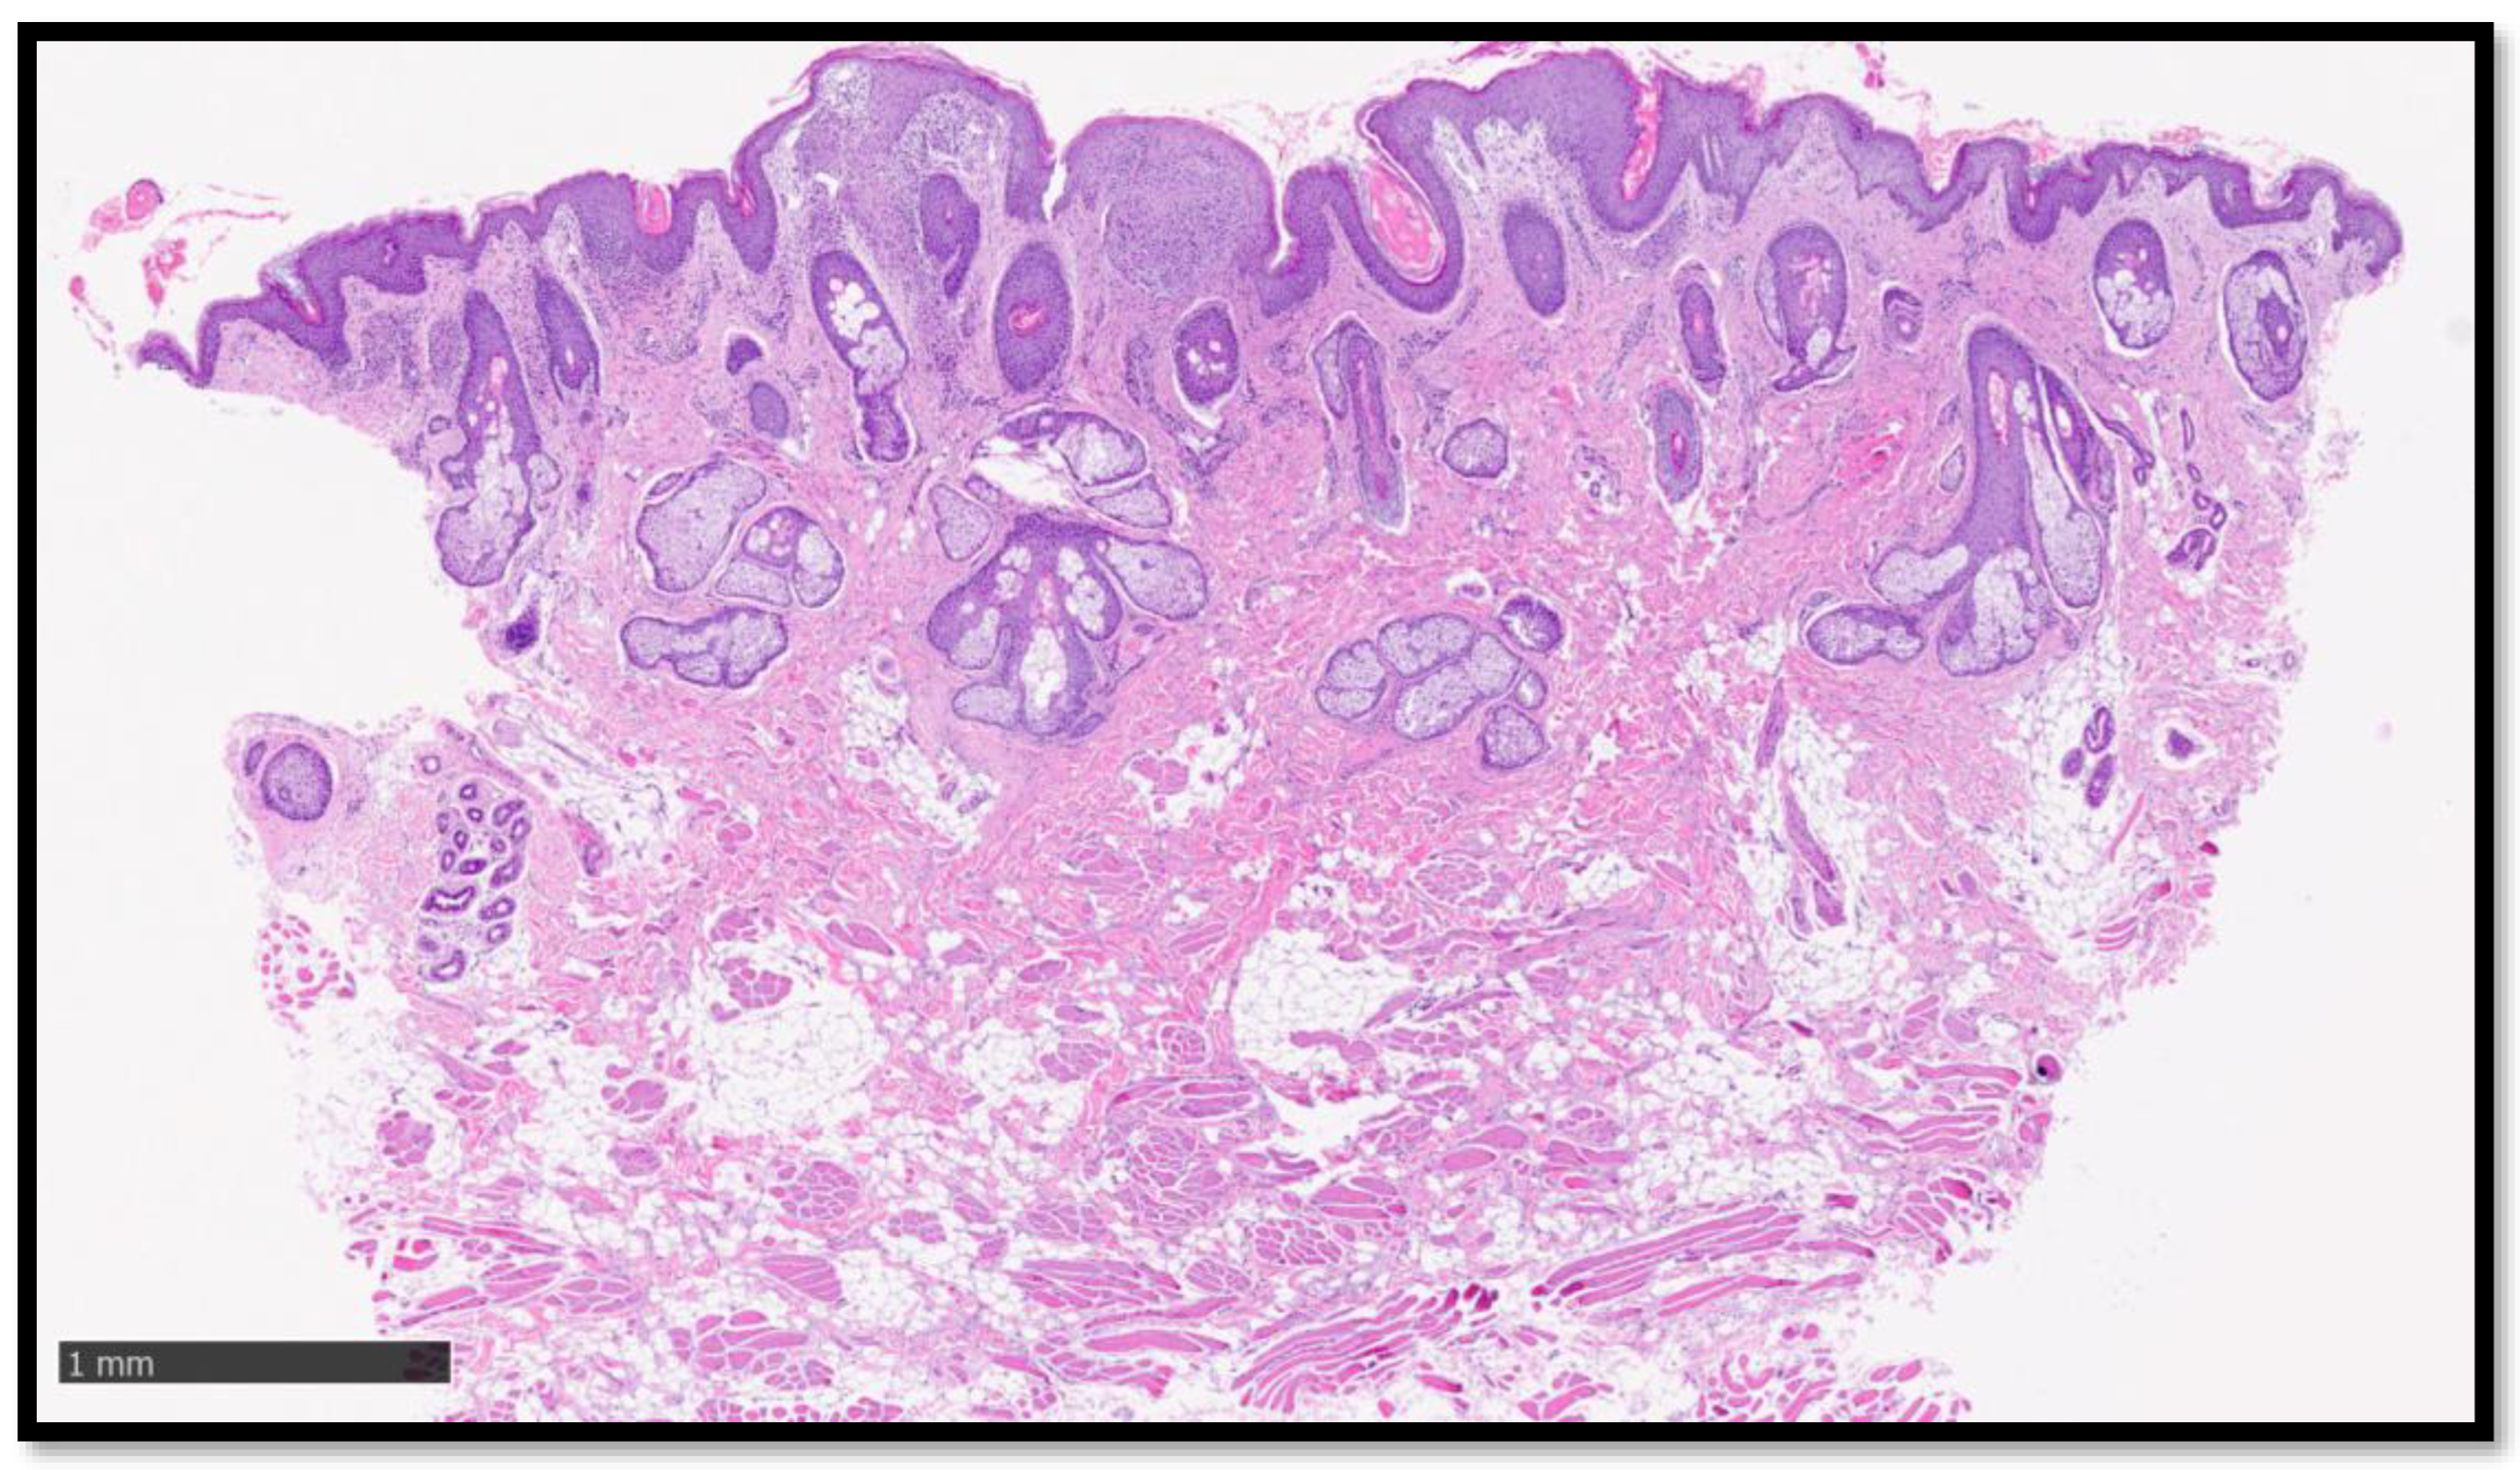

Cazzato, G.; Ambrogio, F.; Foti, C.; Capuzzolo, M.; Trilli, I.; Casatta, N.; Lupo, C.; Carrieri, M.; Daini, D.; Colagrande, A.; et al. Cutaneous Sarcoidosis-like Eruption Following Second Dose of Moderna mRNA-1273 Vaccine: Case or Relationship? Diagnostics 2023, 13, 1286. https://doi.org/10.3390/diagnostics13071286